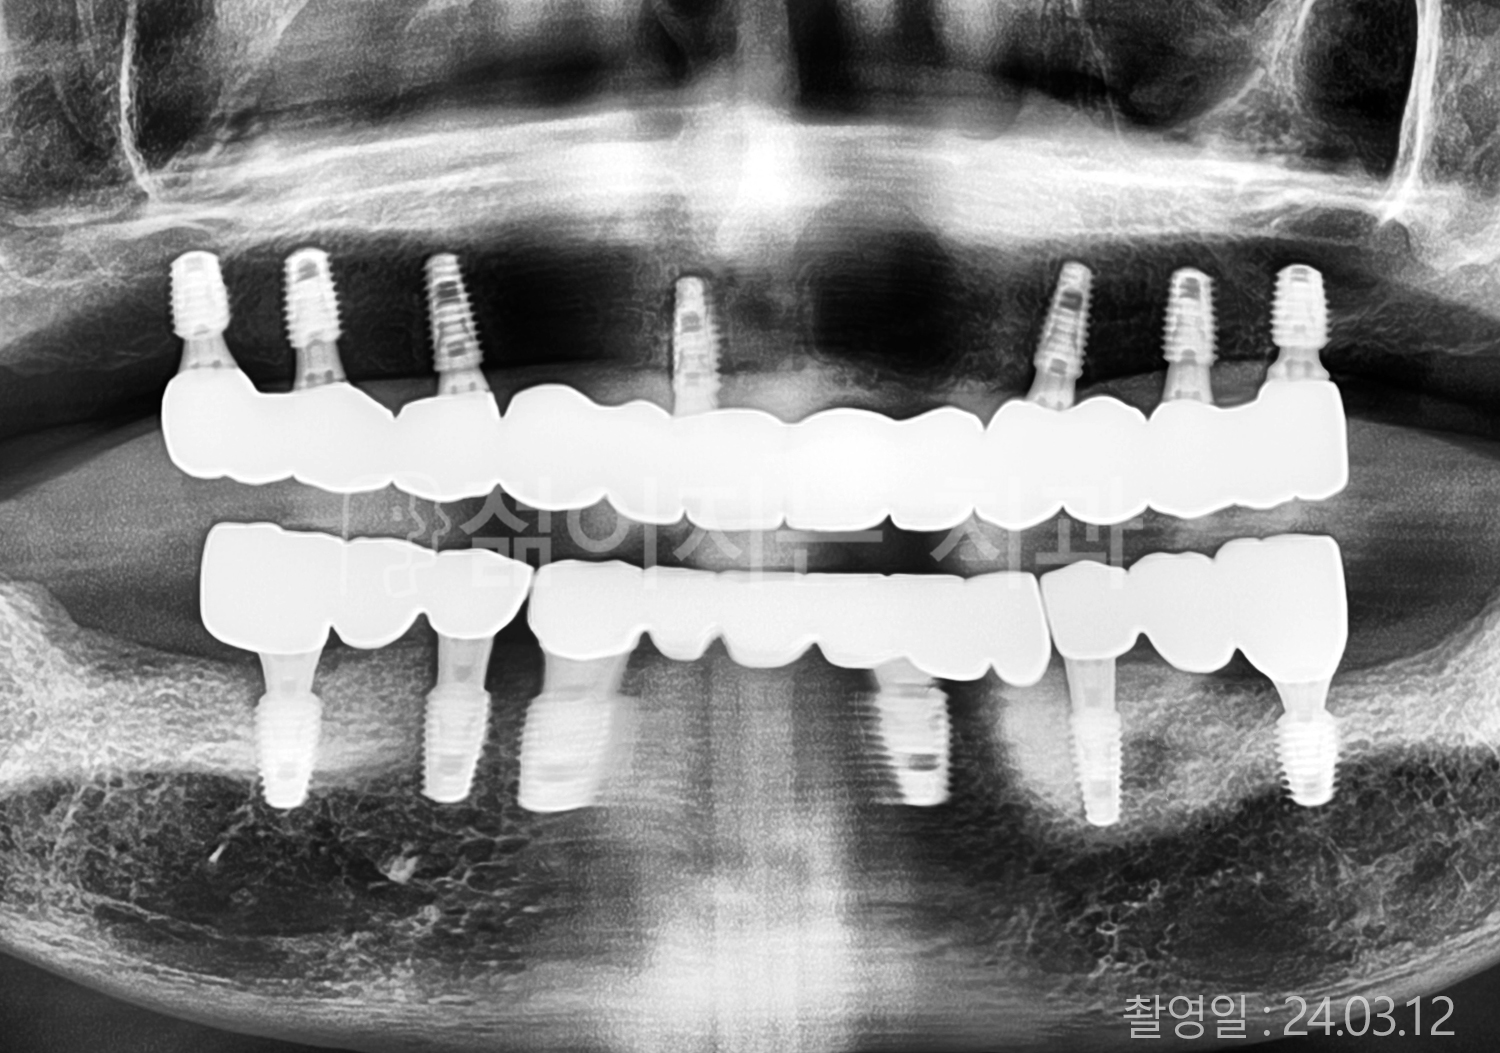

• 70대 고혈압, 당뇨 전체치아 10개 이상 임플란트

• 50대 고혈압, 당뇨 전체치아 10개 이상 임플란트

• 60대 고혈압, 당뇨 전체치아 10개 이상 임플란트

• 50대 전체치아 10개 이상 임플란트

• 70대 당뇨 전체치아 10개 이상 임플란트

• 80대 전체치아 10개 이상 임플란트

• 40대 전체치아 10개 이상 임플란트

• 60대 고협압, 고지혈증 전체치아 10개 이상 임플란트

• 60대 전체치아 10개 이상 임플란트